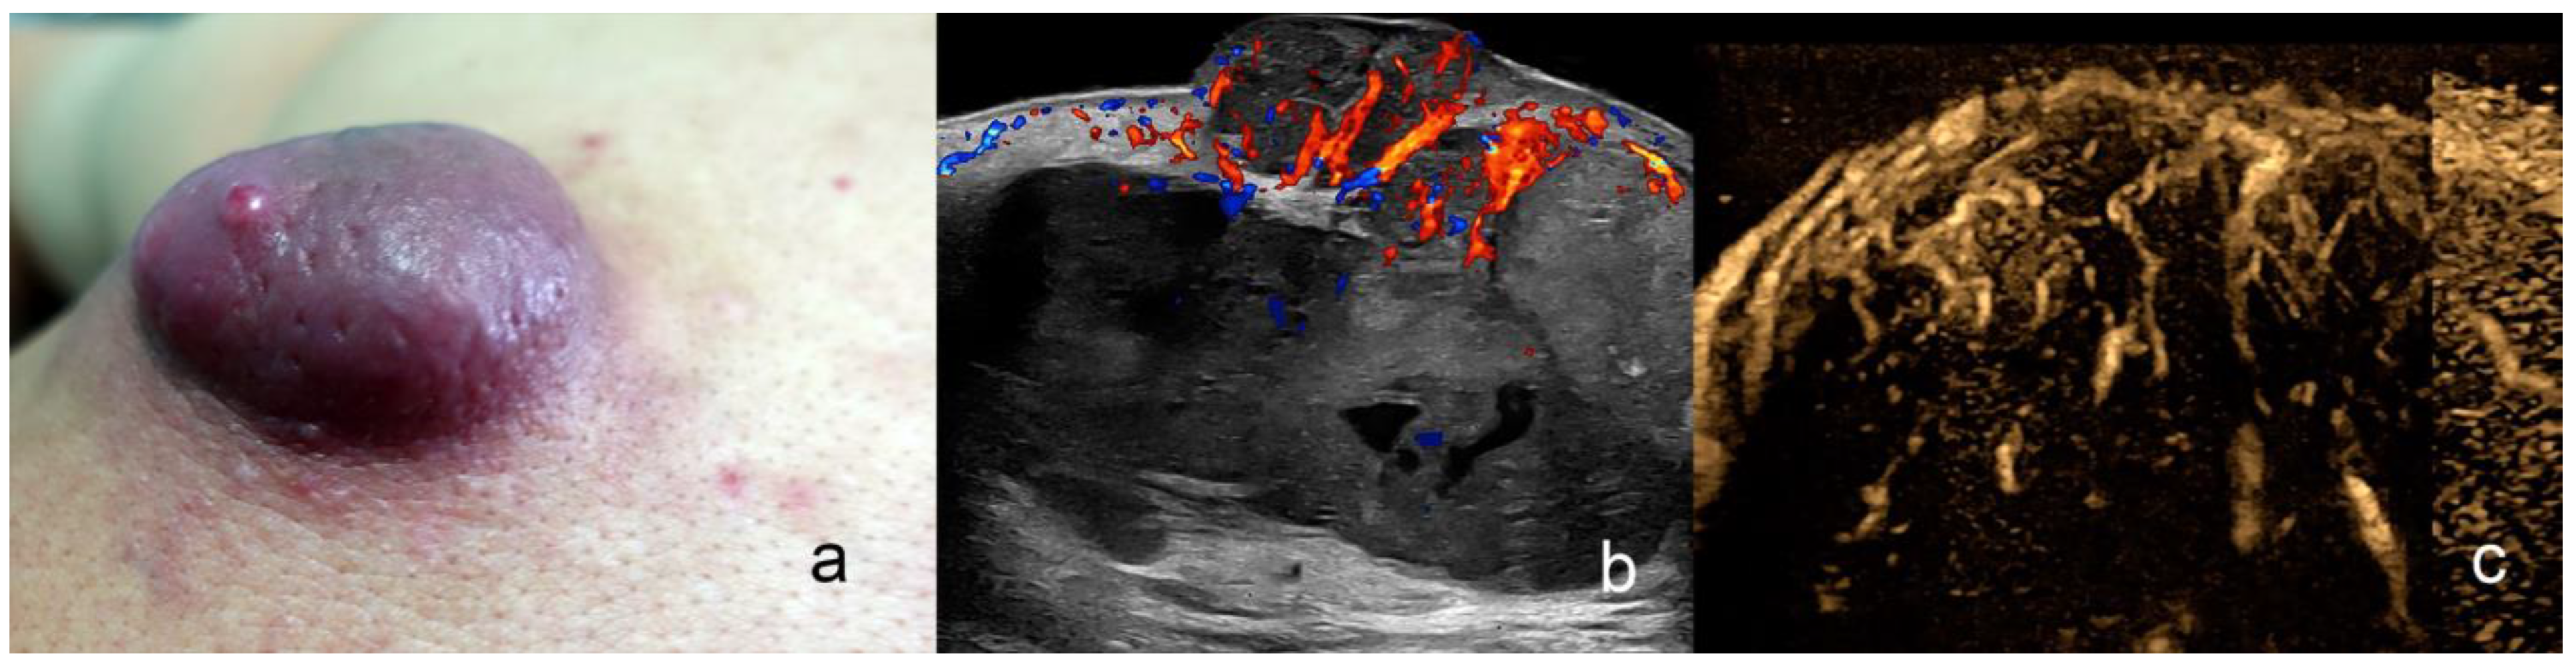

6. Angiosarcoma

| Angiosarcoma | hypoechoic or heterogeneous, ill-defined borders; Kaposi may present a nodular shape | high degree |